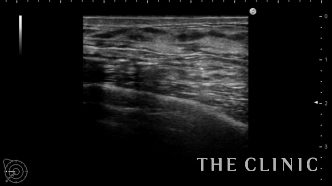

治療後です。画像上しこりは無くなりました。